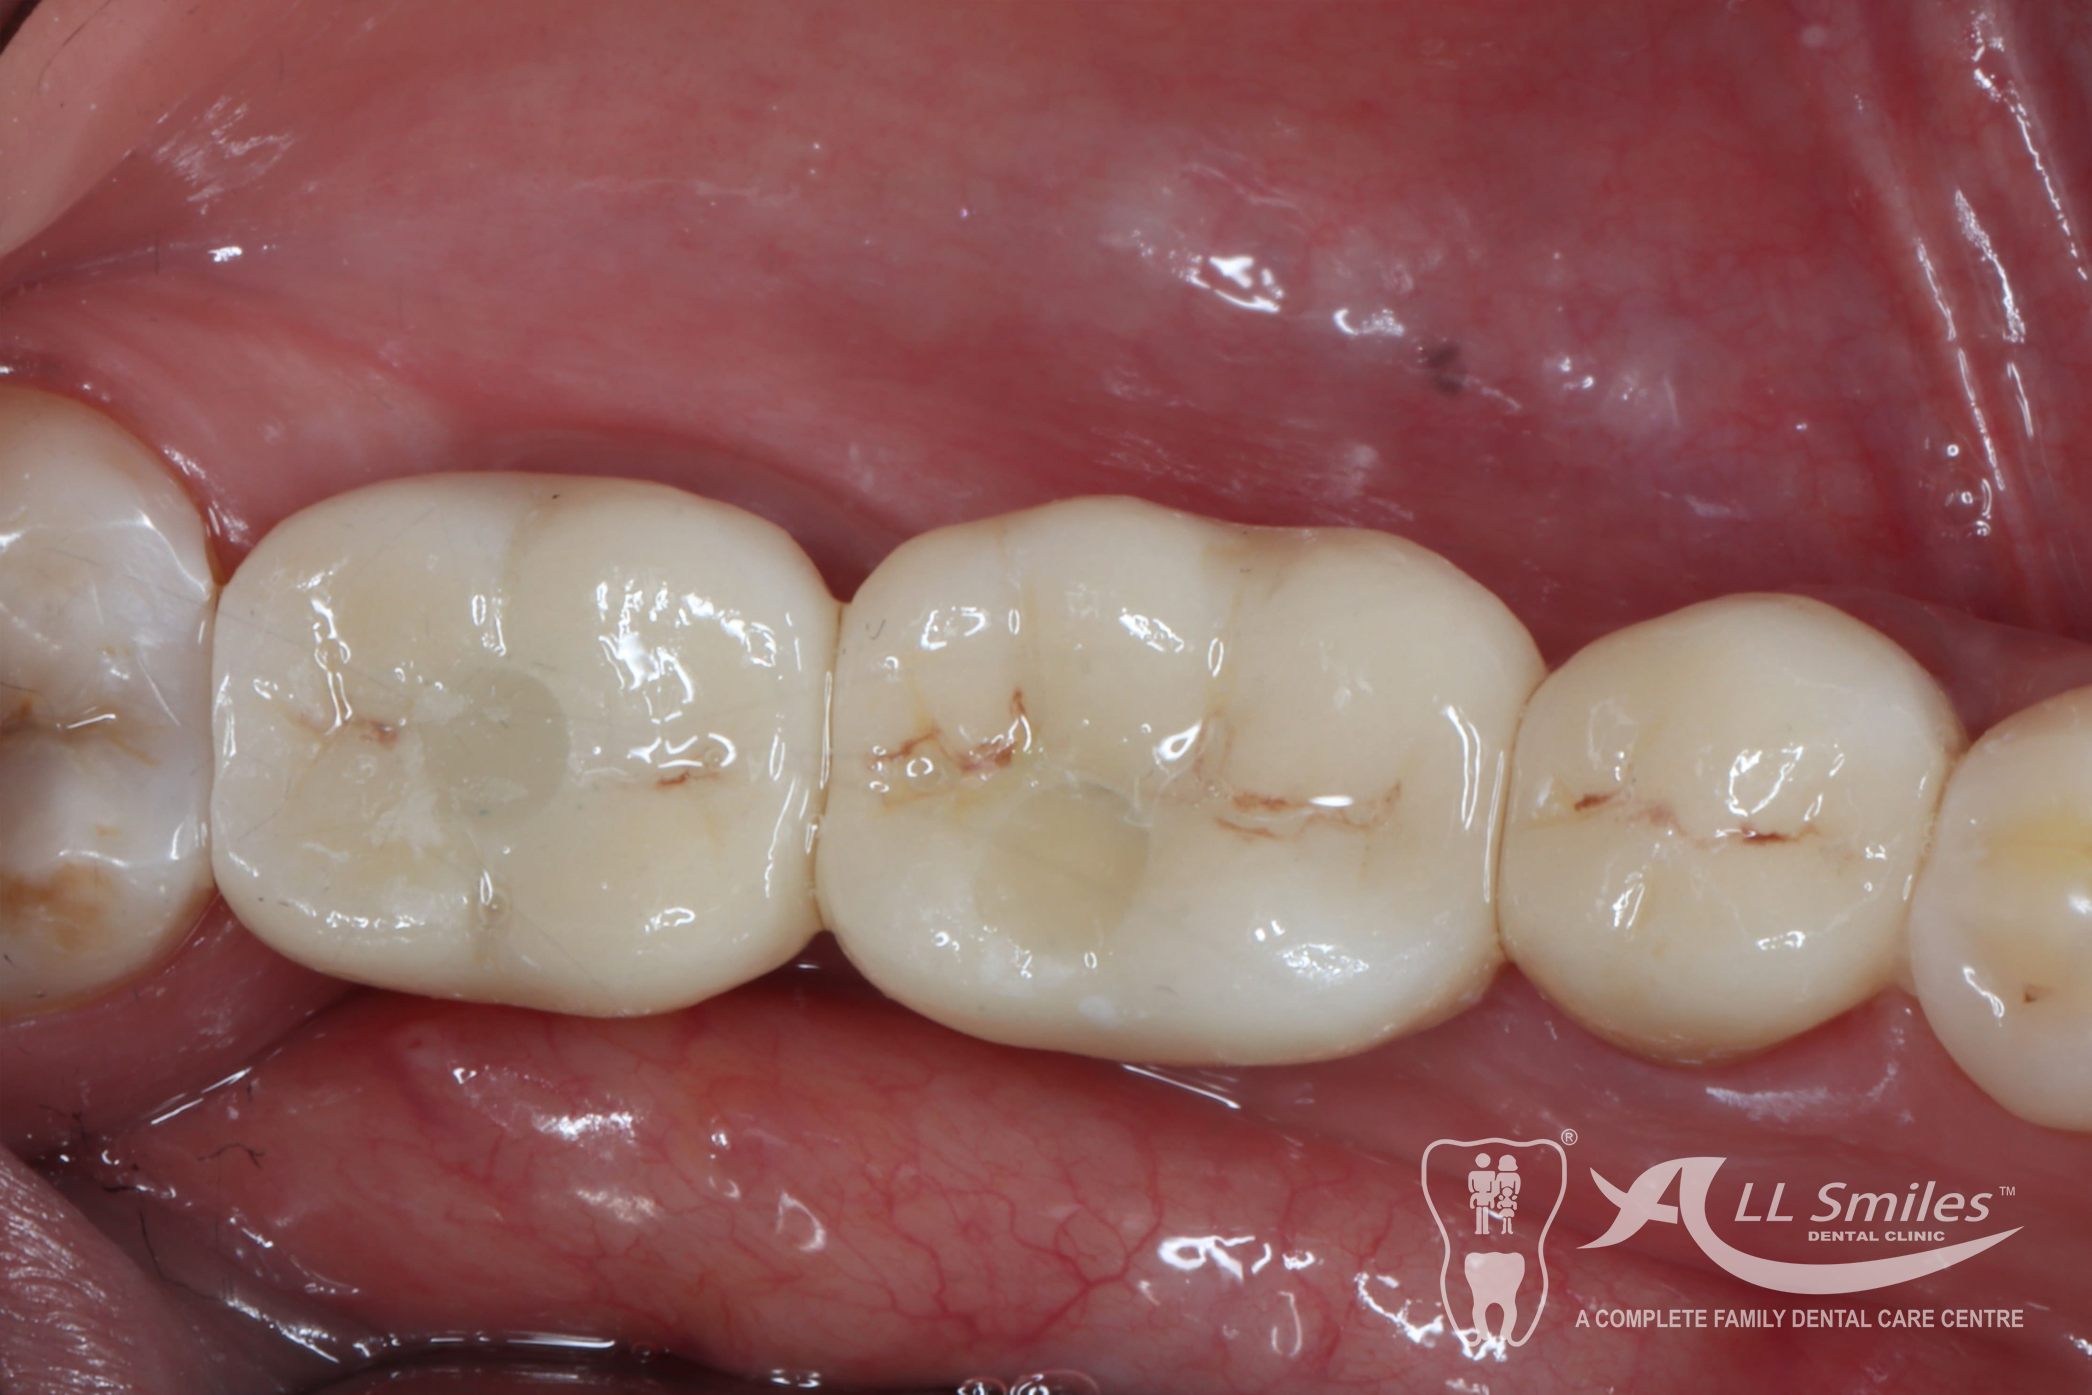

Dental Implants Gallery

Dental implants provide a stable and durable solution for missing teeth that can improve your ability to eat, speak, and smile with confidence. They also help to preserve the surrounding bone tissue and prevent further tooth loss, and they look and feel natural, similar to your natural teeth.